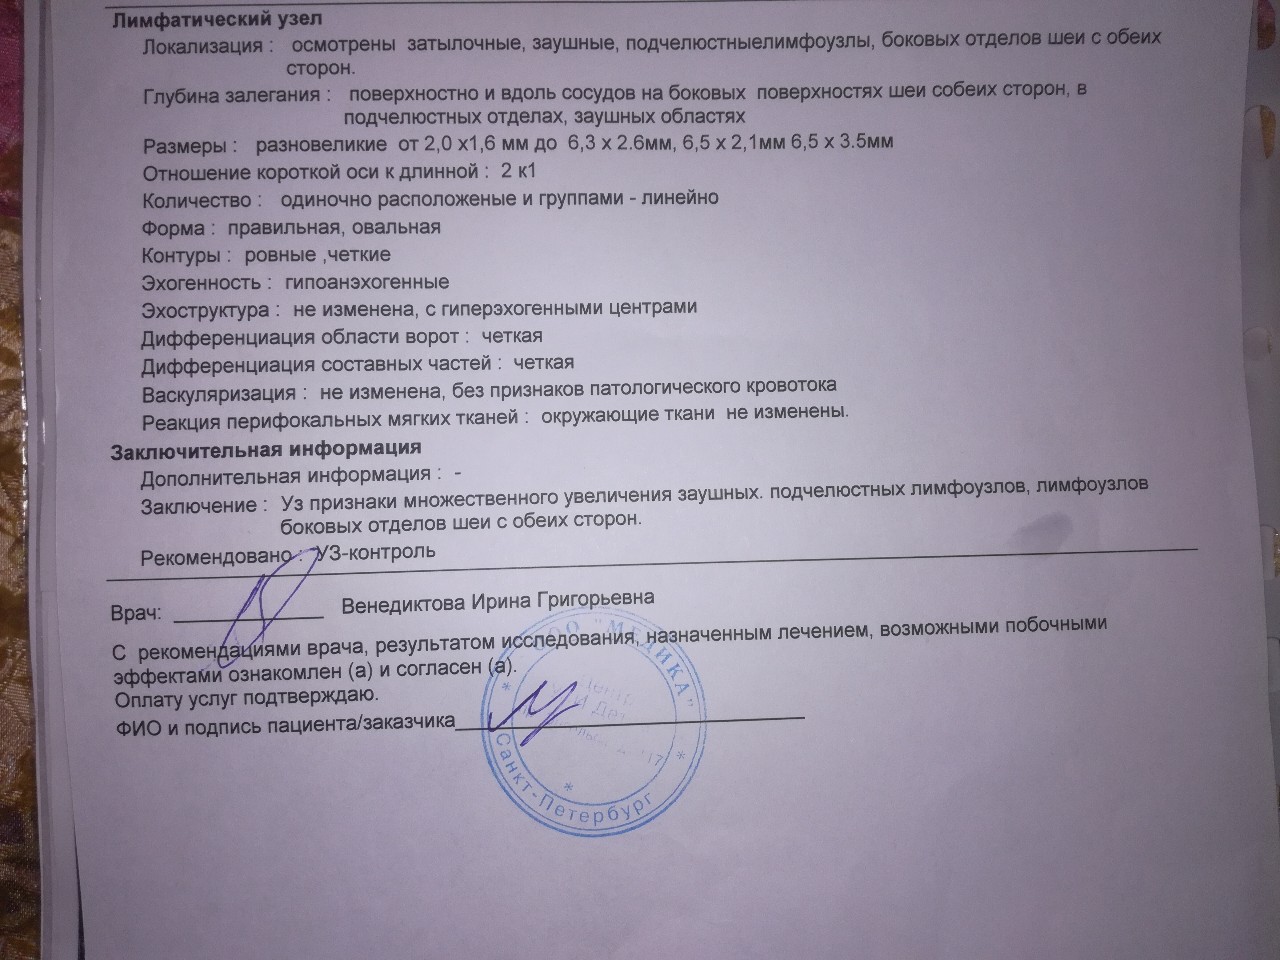

УЗИ лимфоузлов при лимфоме Ходжкина

Раздел: Образы вокруг